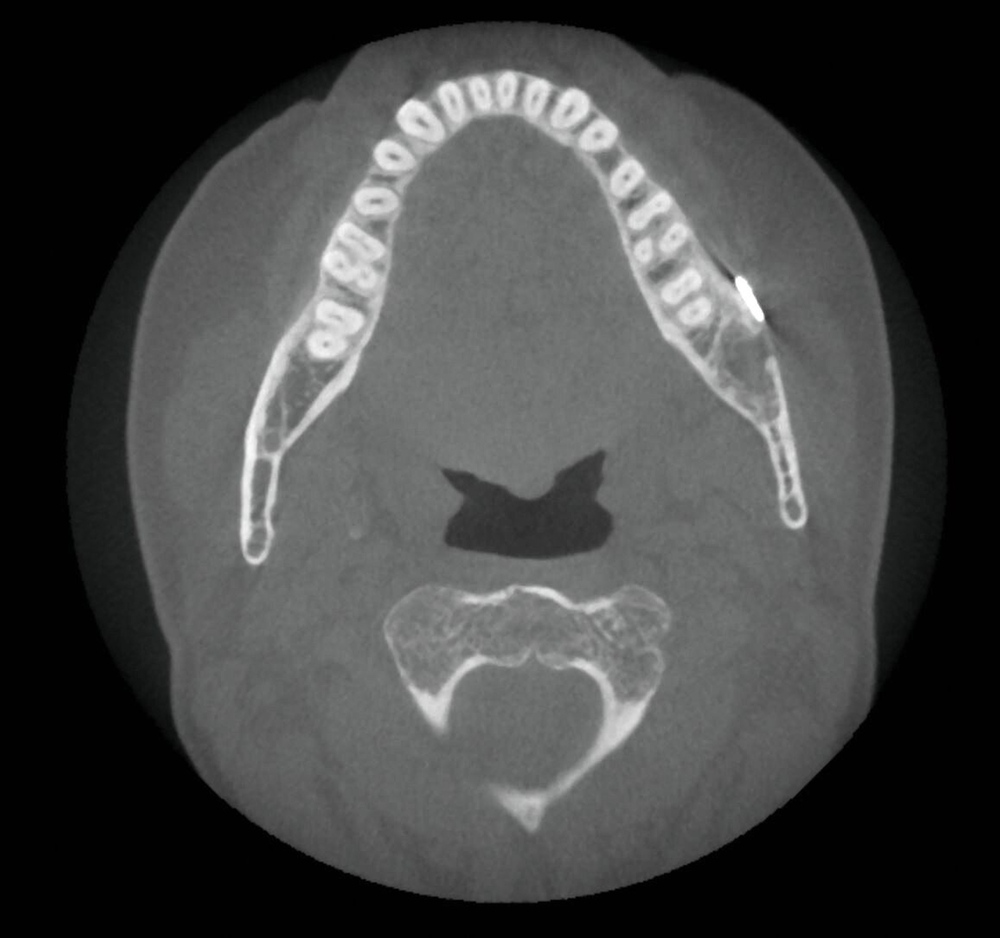

In der dreidimensionalen Bildgebung mit digitaler Volumentomografie (DVT) zeigte sich die intraossäre, scharf abgrenzbare, überwiegend homogen mineralisierte Raumforderung mit zirkulärem, hypodensem Randsaum. Der Nervus alveolaris inferior wurde durch die Läsion nach kranial verdrängt und subtotal ummauert (Abbildung 2). Zur Dignitätssicherung planten wir die vollständige Entfernung der Raumforderung unter Erhalt des Nervus alveolaris inferior in Intubationsnarkose. Eine ausgedehnte Resektion mit Unterkieferkontinuitätsdurchtrennung war aufgrund der unklaren Dignität zum Vorstellungszeitpunkt nicht indiziert.